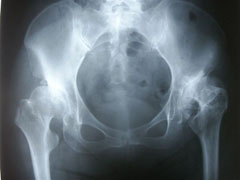

股関節の痛みは、変形性股関節症や大腿骨骨頭壊死、臼蓋形成不全、ペルテスなど骨関節変化のある場合と全くそれのない場合があります。日常でよくみられる股関節の痛みは単純性の股関節炎、股関節周囲炎や、腱炎、滑液包炎などが多いです。

稀にサッカーなどでボールを強く蹴った際に、骨盤から起始している大腿直筋での剥離骨折があるので注意が必要です。

股関節の痛みの原因は様々です。股関節自体、周囲の筋肉の緊張、脊椎・骨盤の歪み、内臓変位によって起きることがあります。股関節特有の突き刺すような痛みを訴えるケースが多いです。そのようなときは内臓、脊椎や骨盤、股関節に関連する筋肉を施術することで股関節の負担がなくなり症状は消えていきます。